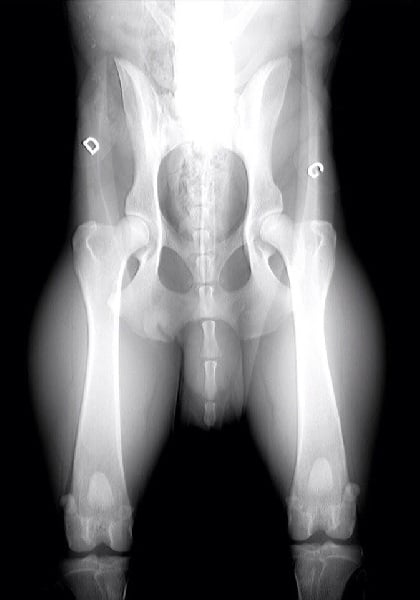

Radiographie des hanches par Dr Haudiquet

Dysplasie des hanches : A/B |